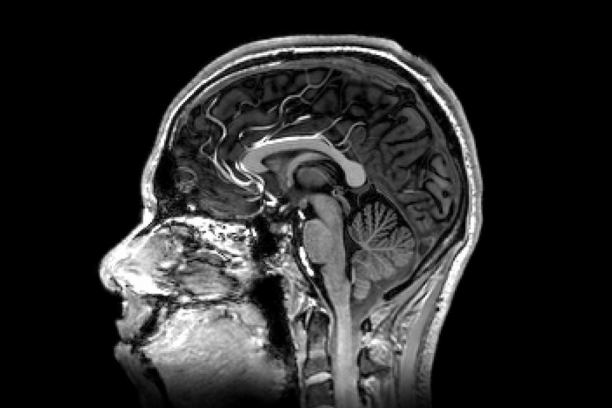

Translationally, we are investigating the effects of body composition in obesity using novel fat-water magnetic resonance imaging (MRI) on neural function, lipoprotein metabolism, vascular function and other endpoints.